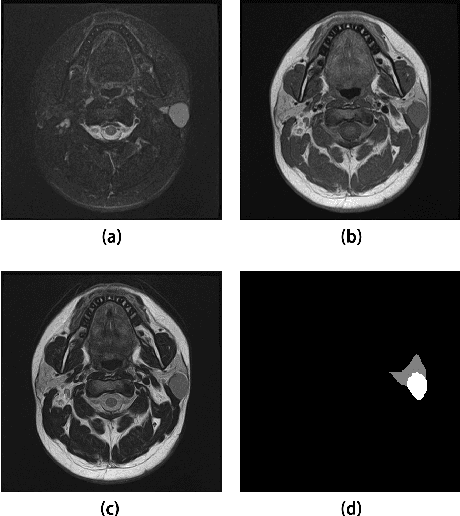

Abstract:Magnetic Resonance Imaging (MRI) plays an important role in diagnosing the parotid tumor, where accurate segmentation of tumors is highly desired for determining appropriate treatment plans and avoiding unnecessary surgery. However, the task remains nontrivial and challenging due to ambiguous boundaries and various sizes of the tumor, as well as the presence of a large number of anatomical structures around the parotid gland that are similar to the tumor. To overcome these problems, we propose a novel anatomy-aware framework for automatic segmentation of parotid tumors from multimodal MRI. First, a Transformer-based multimodal fusion network PT-Net is proposed in this paper. The encoder of PT-Net extracts and fuses contextual information from three modalities of MRI from coarse to fine, to obtain cross-modality and multi-scale tumor information. The decoder stacks the feature maps of different modalities and calibrates the multimodal information using the channel attention mechanism. Second, considering that the segmentation model is prone to be disturbed by similar anatomical structures and make wrong predictions, we design anatomy-aware loss. By calculating the distance between the activation regions of the prediction segmentation and the ground truth, our loss function forces the model to distinguish similar anatomical structures with the tumor and make correct predictions. Extensive experiments with MRI scans of the parotid tumor showed that our PT-Net achieved higher segmentation accuracy than existing networks. The anatomy-aware loss outperformed state-of-the-art loss functions for parotid tumor segmentation. Our framework can potentially improve the quality of preoperative diagnosis and surgery planning of parotid tumors.

Abstract:Parotid gland tumors account for approximately 2% to 10% of head and neck tumors. Preoperative tumor localization, differential diagnosis, and subsequent selection of appropriate treatment for parotid gland tumors is critical. However, the relative rarity of these tumors and the highly dispersed tissue types have left an unmet need for a subtle differential diagnosis of such neoplastic lesions based on preoperative radiomics. Recently, deep learning methods have developed rapidly, especially Transformer beats the traditional convolutional neural network in computer vision. Many new Transformer-based networks have been proposed for computer vision tasks. In this study, multicenter multimodal parotid gland MRI images were collected. The Swin-Unet which was based on Transformer was used. MRI images of STIR, T1 and T2 modalities were combined into a three-channel data to train the network. We achieved segmentation of the region of interest for parotid gland and tumor. The DSC of the model on the test set was 88.63%, MPA was 99.31%, MIoU was 83.99%, and HD was 3.04. Then a series of comparison experiments were designed in this paper to further validate the segmentation performance of the algorithm.